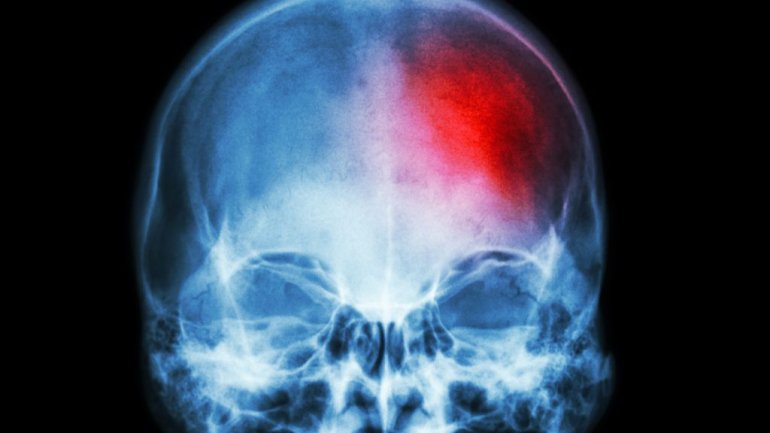

Τα άτομα που εργάζονται για πολλές ώρες έχουν μεγαλύτερο κίνδυνο εμφάνισης εγκεφαλικού επεισοδίου, ειδικά αν εργάζονται πολλές ώρες για 10 ή περισσότερα χρόνια.

Οι συμμετέχοντες που εργάζονταν για πολλές ώρες είχαν 29% μεγαλύτερο κίνδυνο εμφάνισης εγκεφαλικού επεισοδίου, και εκείνοι που εργάζονταν πολύ για 10 χρόνια ή περισσότερο είχαν 45% μεγαλύτερο κίνδυνο εμφάνισης εγκεφαλικού επεισοδίου.